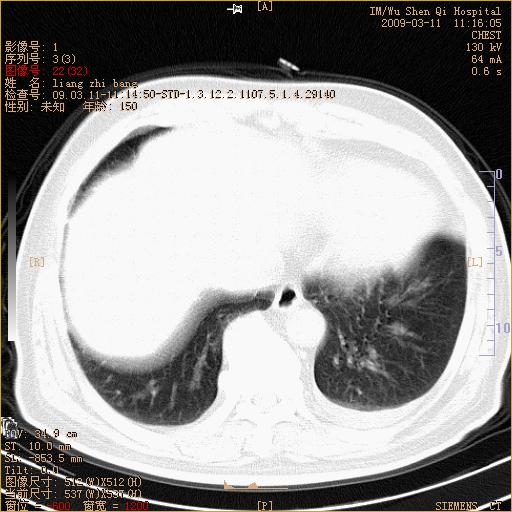

标题: CT18604:男,60岁,咳嗽一月余 [打印本页]

标题: CT18604:男,60岁,咳嗽一月余

1)考虑左肺上叶中央型肺癌并左肺上叶肺不张;建议必要时行纤支镜检查进一步明确诊断。2)左侧胸腔积液。

肺门肿块、支气管开口闭塞伴肺不张及胸水!典型的中心型肺癌变现!

1、左肺上叶中央型肺癌并上叶阻塞性肺不张。

2、左侧胸腔少量积液,右侧胸膜轻度增厚。

左肺们肿块并左肺上叶不张。考虑左肺中心性肺癌并左肺上叶不张及左侧胸腔积液